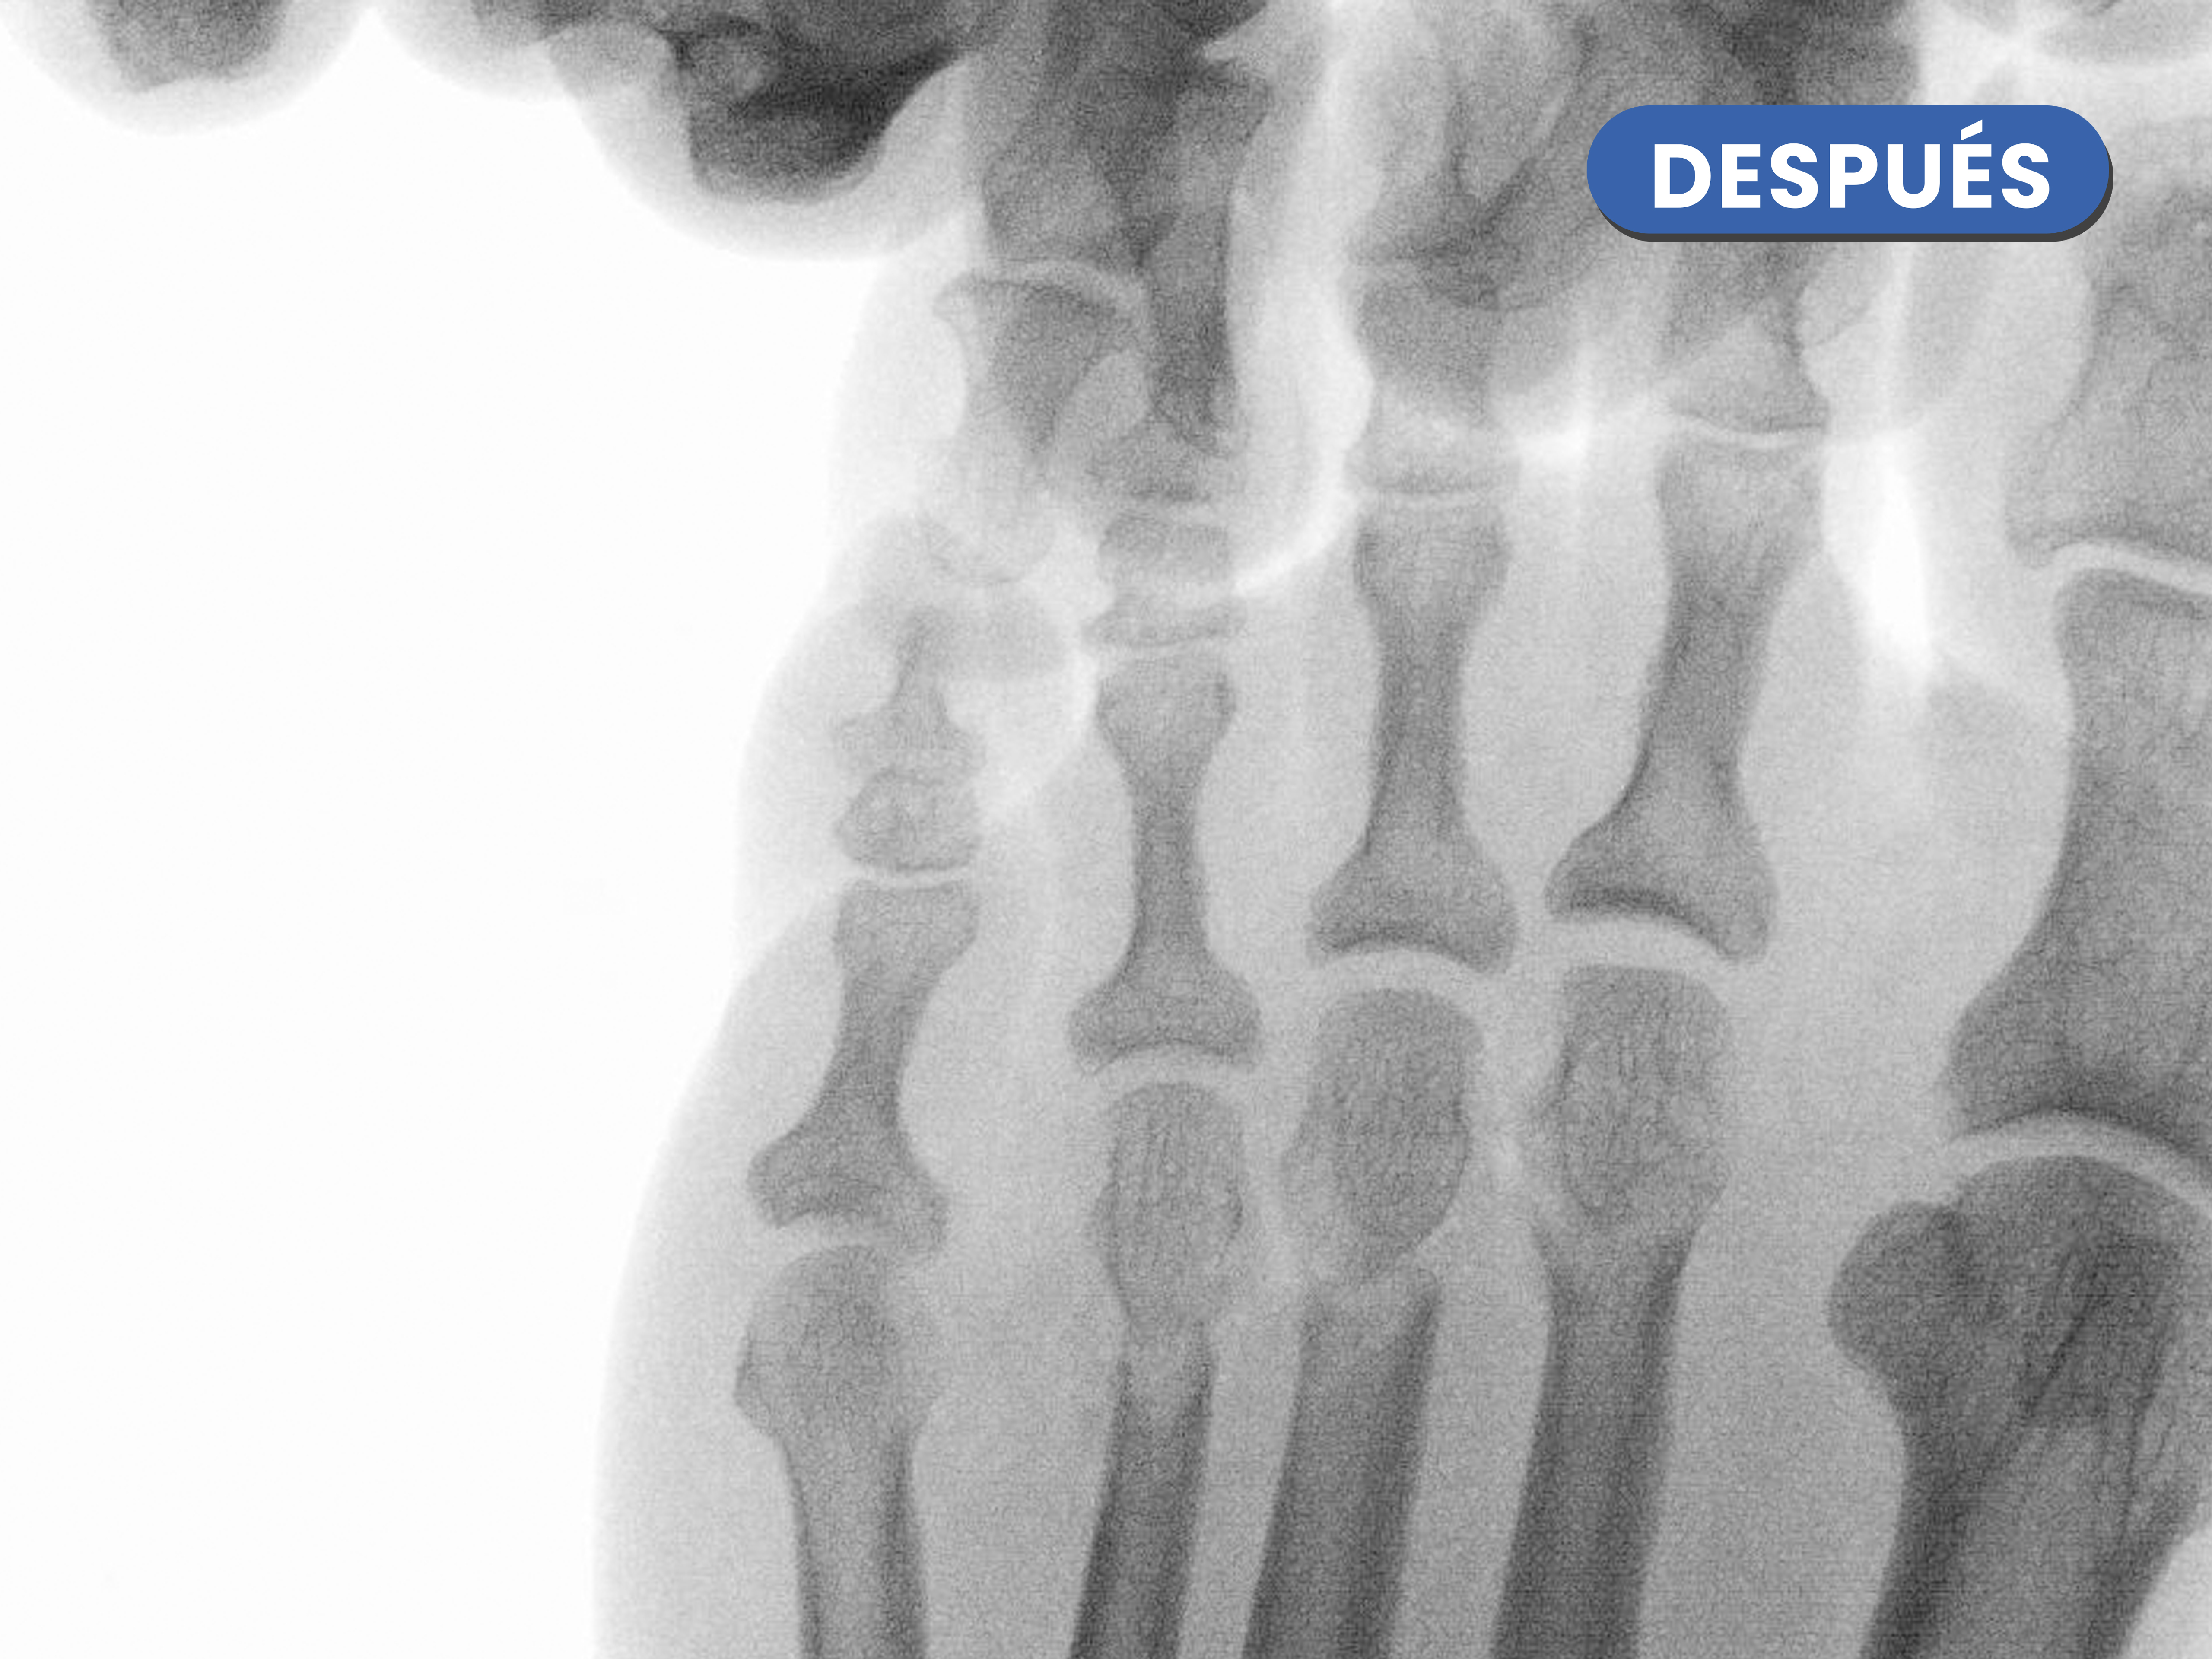

Casos reales resueltos con Cirugía de Mínima Incisión (CMI)

Te mostramos casos reales resueltos mediante cirugía de mínima incisión por el Dr. Rubén Lorca y su equipo.

Mueve las flechas para visualizar el antes y después.

En este caso destaca la corrección metatarsofalángica tras la realización de la osteotomía metatarsal y osteotomía de la falange proximal del cuarto dedo, generandose esa línea o espacio articular entre ambos.